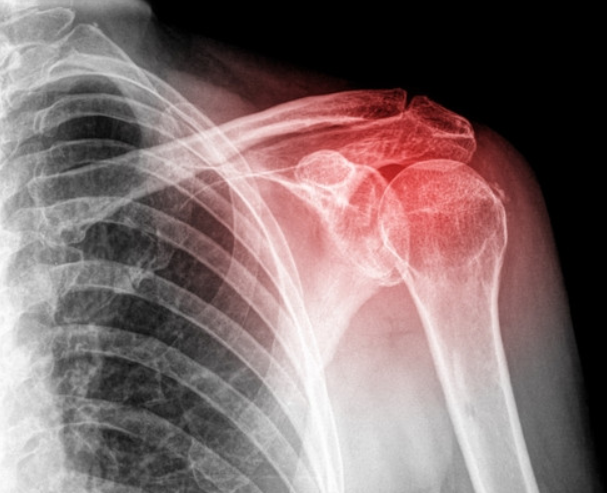

▣ 어깨는뼈는 크게 3가지입니다.

어깨 상완골(긴팔뼈)

쇄골

견갑골